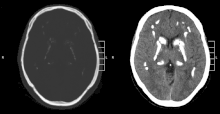

| CT scan of characteristic calcifications of the disease | |

Primary familial brain calcification[1] (PFBC), also known as familial idiopathic basal ganglia calcification (FIBGC) and Fahr's disease,[1] is a rare,[2] genetically dominant or recessive, inherited neurological disorder characterized by abnormal deposits of calcium in areas of the brain that control movement. Through the use of CT scans, calcifications are seen primarily in the basal ganglia and in other areas such as the cerebral cortex.[3]

Brain CT scan is the preferred method of localizing and assessing the extent of cerebral calcifications.

The calcification is usually identified on CT scan but may be visible on plain films of the skull.